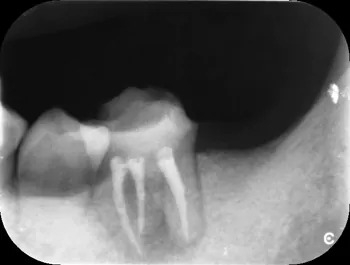

根管充填直後01

| 治療経過 | ラバーダム防湿を行い、マイクロスコープを用いて滅菌下で精密な根管治療を行いました。根管内部を完全にきれいにした後、細菌が繁殖しない様に内部を緊密に封鎖(根管充填)をしました。直後はまだ透過像を認めますが、3ヶ月経過後は炎症もほとんど認められず、症状も改善されていました。 患者さんも抜歯をせずに済んだ為、喜んでいました。現在はラバーダム防湿やマイクロスコープ、また場合によってはCT撮影をする事で今までの治療では見落としていた問題を見つける事ができるようになって、治療の成功率を上げることができます。 |